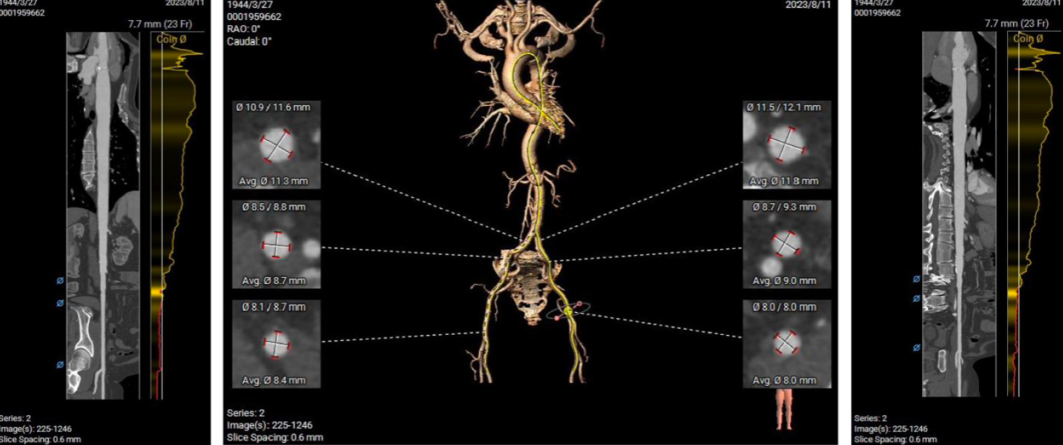

CT分析

主动脉根部:

主动脉根部径线:

Annulus23.7mm

LVOT23.6mm

L28.4*R27.4*N28.8

SOVP89.9mm

STJ26.6mm

AA31.9mm

LV39.8mm

LV40.6mm

多平面分析:

Sub-223.8mm

Super-223.7mm

Super-425.2mm

Super-624.3mm

Super-825.4mm

Super-1025.4mm

双侧冠脉开口高度可,左侧瓣叶略长,预估左侧冠脉遮挡风险较低:

中度高位钙化,钙化分布较均匀,瓣膜锚定力可,形态影响较小:

投照角度:

右窦中心

右11足16

左冠切线

左8头13

左右重合

右33足41

左心耳及心室未见血栓,瓣环水平夹角57°,近横位心:

膜部室间隔2.2mm,主瓣二尖瓣夹角可:

主动脉弓角及弓距可,预估输送器可顺利过弓,必要时Snare辅助:

入路血管走形良好,双侧髂股动脉内径可,入路血管散在附壁钙化,整体入路条件良好: